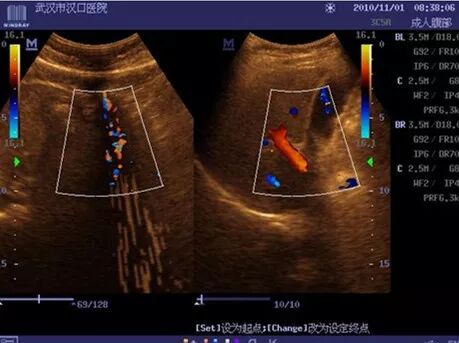

3、DC-6干扰

现象:二维图像波纹干扰;彩色取样框内条状干扰;

处理措施:更换发射板,故障解决